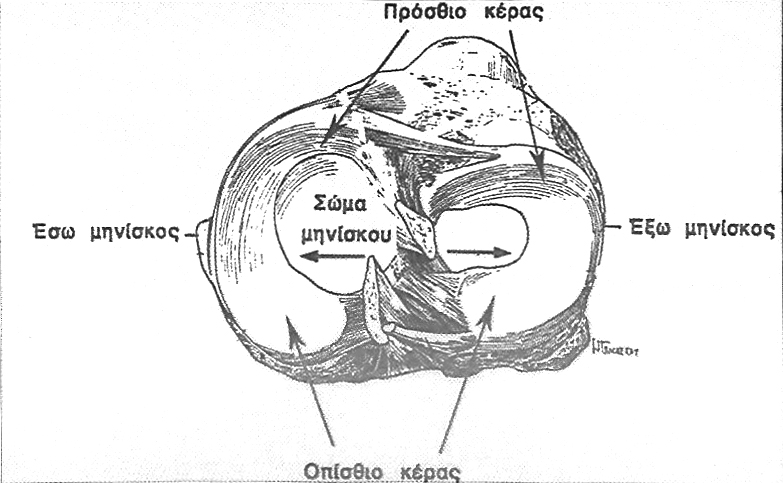

Οι μηνίσκοι είναι δύο για κάθε γόνατο, ο έσω και ο έξω και παρεμβάλλονται μεταξύ μηρού και κνήμης. Έχουν μορφή ημισελινοειδή, ο έξω μηνίσκος ομοιάζει περισσότερο με κλειστό κύκλο. Ο κάθε μηνίσκος αποτελείται από το σώμα και τα δύο κέρατα, το πρόσθιο και το οπίσθιο (εικόνα 1). Η διατομή τους είναι σφηνοειδής, με τη βάση προς την περιφέρεια όπου προσφύονται με το θύλακο και με την κνήμη με τους κορωνοειδείς συνδέσμους. Η επάνω επιφάνεια του μηνίσκου είναι κοίλη, ενώ η κάτω είναι επίπεδη. Ο έξω μηνίσκος είναι περισσότερο κινητός, γι’αυτό τραυματίζεται σπανιότερα.